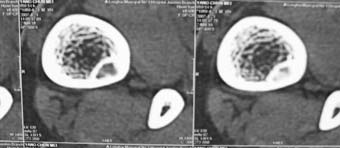

男,中学生打篮球时右踝扭伤,拍片时发右胫骨下端楕圆形透亮影,是不是动脉瘤样骨囊肿,请讨论

骨皮质内破坏区,其下部可能为“巢中有蛋“征,首先考虑骨样骨瘤,本病须与骨皮质脓肿,硬化性骨髓炎、骨梅毒等疾病鉴别。请结合临床进一步鉴别。

胫骨后外侧见囊样低密度边缘硬化,其内见小点状高密度影,首先考虑骨样骨瘤

应该是比较典型的非骨化性纤维瘤:病灶偏于骨干的一侧,紧靠皮质下,呈类圆形,靠近髓腔侧有硬化边,病灶长轴平行于骨干,周围无骨膜反应和软组织肿块。与骨样骨瘤鉴别:后者具有明显或剧烈疼痛,“瘤巢”为其特征,在瘤巢周围有显著的反应性骨质增生。